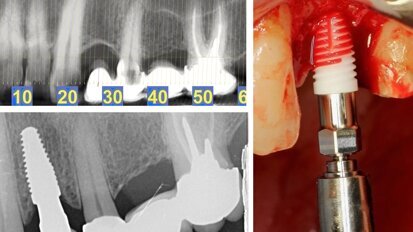

Tecnología para el éxito en cirugía bucal e implantología

La Sociedad Española de Cirugía Bucal celebró en Sierra Nevada la VI Reunión de Invierno SECIB los días 1 y 2 de marzo. La gestión y las nuevas ...